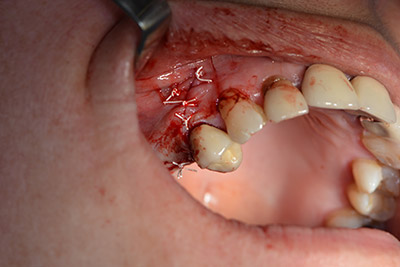

Danach wird das Implantat eingebracht und der Knochen aufgebaut. Aufgrund der Größe des Augmentates wurde im vorliegenden Fall Eigenknochen, der als Bohrspäne bei der Implantation 16 und der Fenestration 14 angefallen ist und mit einer Knochenfalle aufgefangen wurde, mit Knochenersatzmaterial vermischt.

Eine resorbierbare Membran bildet die Barriere nach bukkal und deckt das Augmentat ab. Zum Schluss wird speicheldicht vernäht. (Abb. 15 bis 19).

Augmentation mit Eigenknochen

Abb. 15

Abb. 16

Implantation

Abb. 17

Implantologie

Abb. 18

speicheldichter Wundverschluss.

Abb. 19